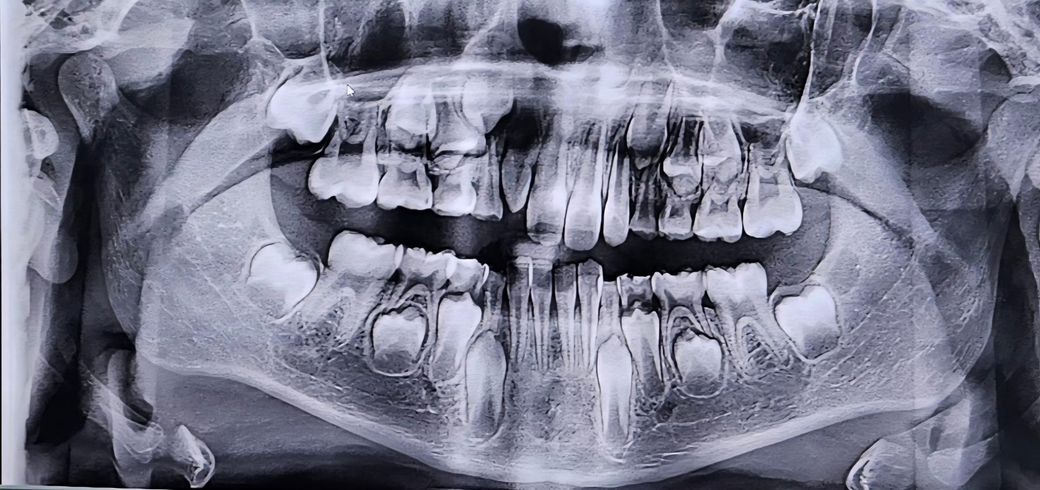

앵글 분류 몇단계 일까요? 대략이라도 부탁드립니다ㅜㅜ

9살아이입니다. 지금은 치료해도 큰 효과를 기대하기 어렵다고 영구치가 다 날때까지 지켜보자 하시는데 보험이 들어있어서 궁금해요ㅜㅜ

• 1번 째 사진

앵글분류는 파노라마 상으로는 알수 없고 아직 유치열기라 판단하기가 어렵습니다. 조금더 성장해야 될것같습니다.

교합의 유무를 확인하는 앵글 분류를 확인하기 위해서는 파노라마 사진보다 측면에 새팔로 사진이 필요합니다.

파노라마 사진으로는 교합 유형의 종류를 파악하기 힘듭니다

위 사진으로는 앵글 분류를 알 수는 없습니다. 치과 내원하셔서 검사 해보시는 것이 좋겠습니다.

이 사진만 봐서는 정확히 알기 어렵습니다 셉 사진과 모형채득해서 분석합니다

angle class I 으로 예상됩니다

일반적으로 심한 부정교합, 구순구개 등이 아니면 교정은 보험적용 안됩니다 잘 알아보시기 바랍니다